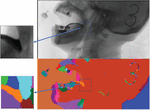

images

Figure 9 Taking the cervical spine as the coordinate system.

Figure 10 Taking the cervical spine as the coordinate system (enlarged display).

Through observation, we can find that the position of the cervical spine has a relatively high degree of recognition. We can calibrate the position of the cervical spine to track the movement trajectory of the fluid barium. As a model verification and correction link, it will help us to improve the recognition accuracy. Experimental results As shown in the figure below.